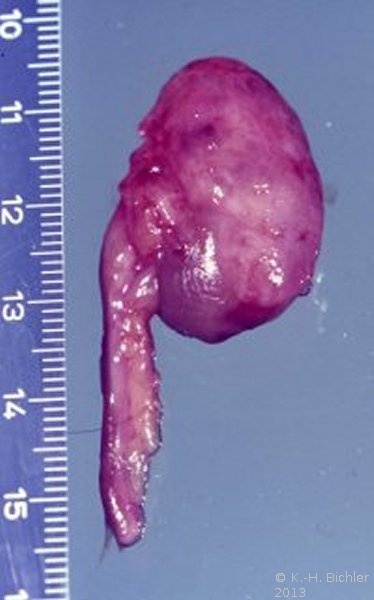

Es handelt sich pathologisch-anatomisch um eine kleine Niere mit einem Gewicht um 30g. Dabei sind die funktionellen Elemente (Renculi) numerisch reduziert auf 3 bis 5, normal 12 bis 14. Die Organanteile sind aber normal entwickelt (

Im Gegensatz zum in der Abbildung beschriebenen Beispiel besteht bei der Aplasie oder Dysplasie ein unvollständiges Gewebe mit erhaltenem fetalen Anteil (Abbildung 21).

Die echte Hypoplasie hat keine Komplikationen wie Hypertonie. Sie wird in der Regel zufällig entdeckt, im Gegensatz zur einseitigen pyelonephritischen Zwergniere mit Hypertonie. Die echte hypoplastische Niere ist selten. Zollinger fand unter 10.000 Obduktionen eine hypoplastische Niere. Die erworbenen Zwergnieren infolge entzündlicher oder vaskulärer Ursachen sind dagegen häufiger.